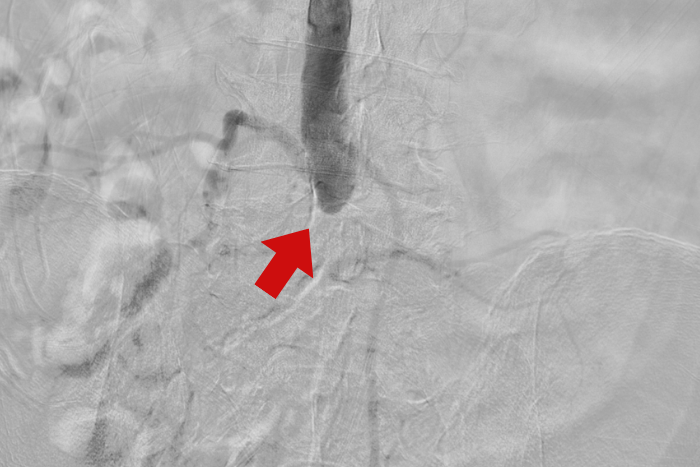

(Dân trí) - Chủ quan với những cơn đau chân kéo dài, người đàn ông 70 tuổi chỉ nhập viện khi các ngón chân đã hoại tử, có nguy cơ phải cắt cụt chi do tắc mạch máu nghiêm trọng.